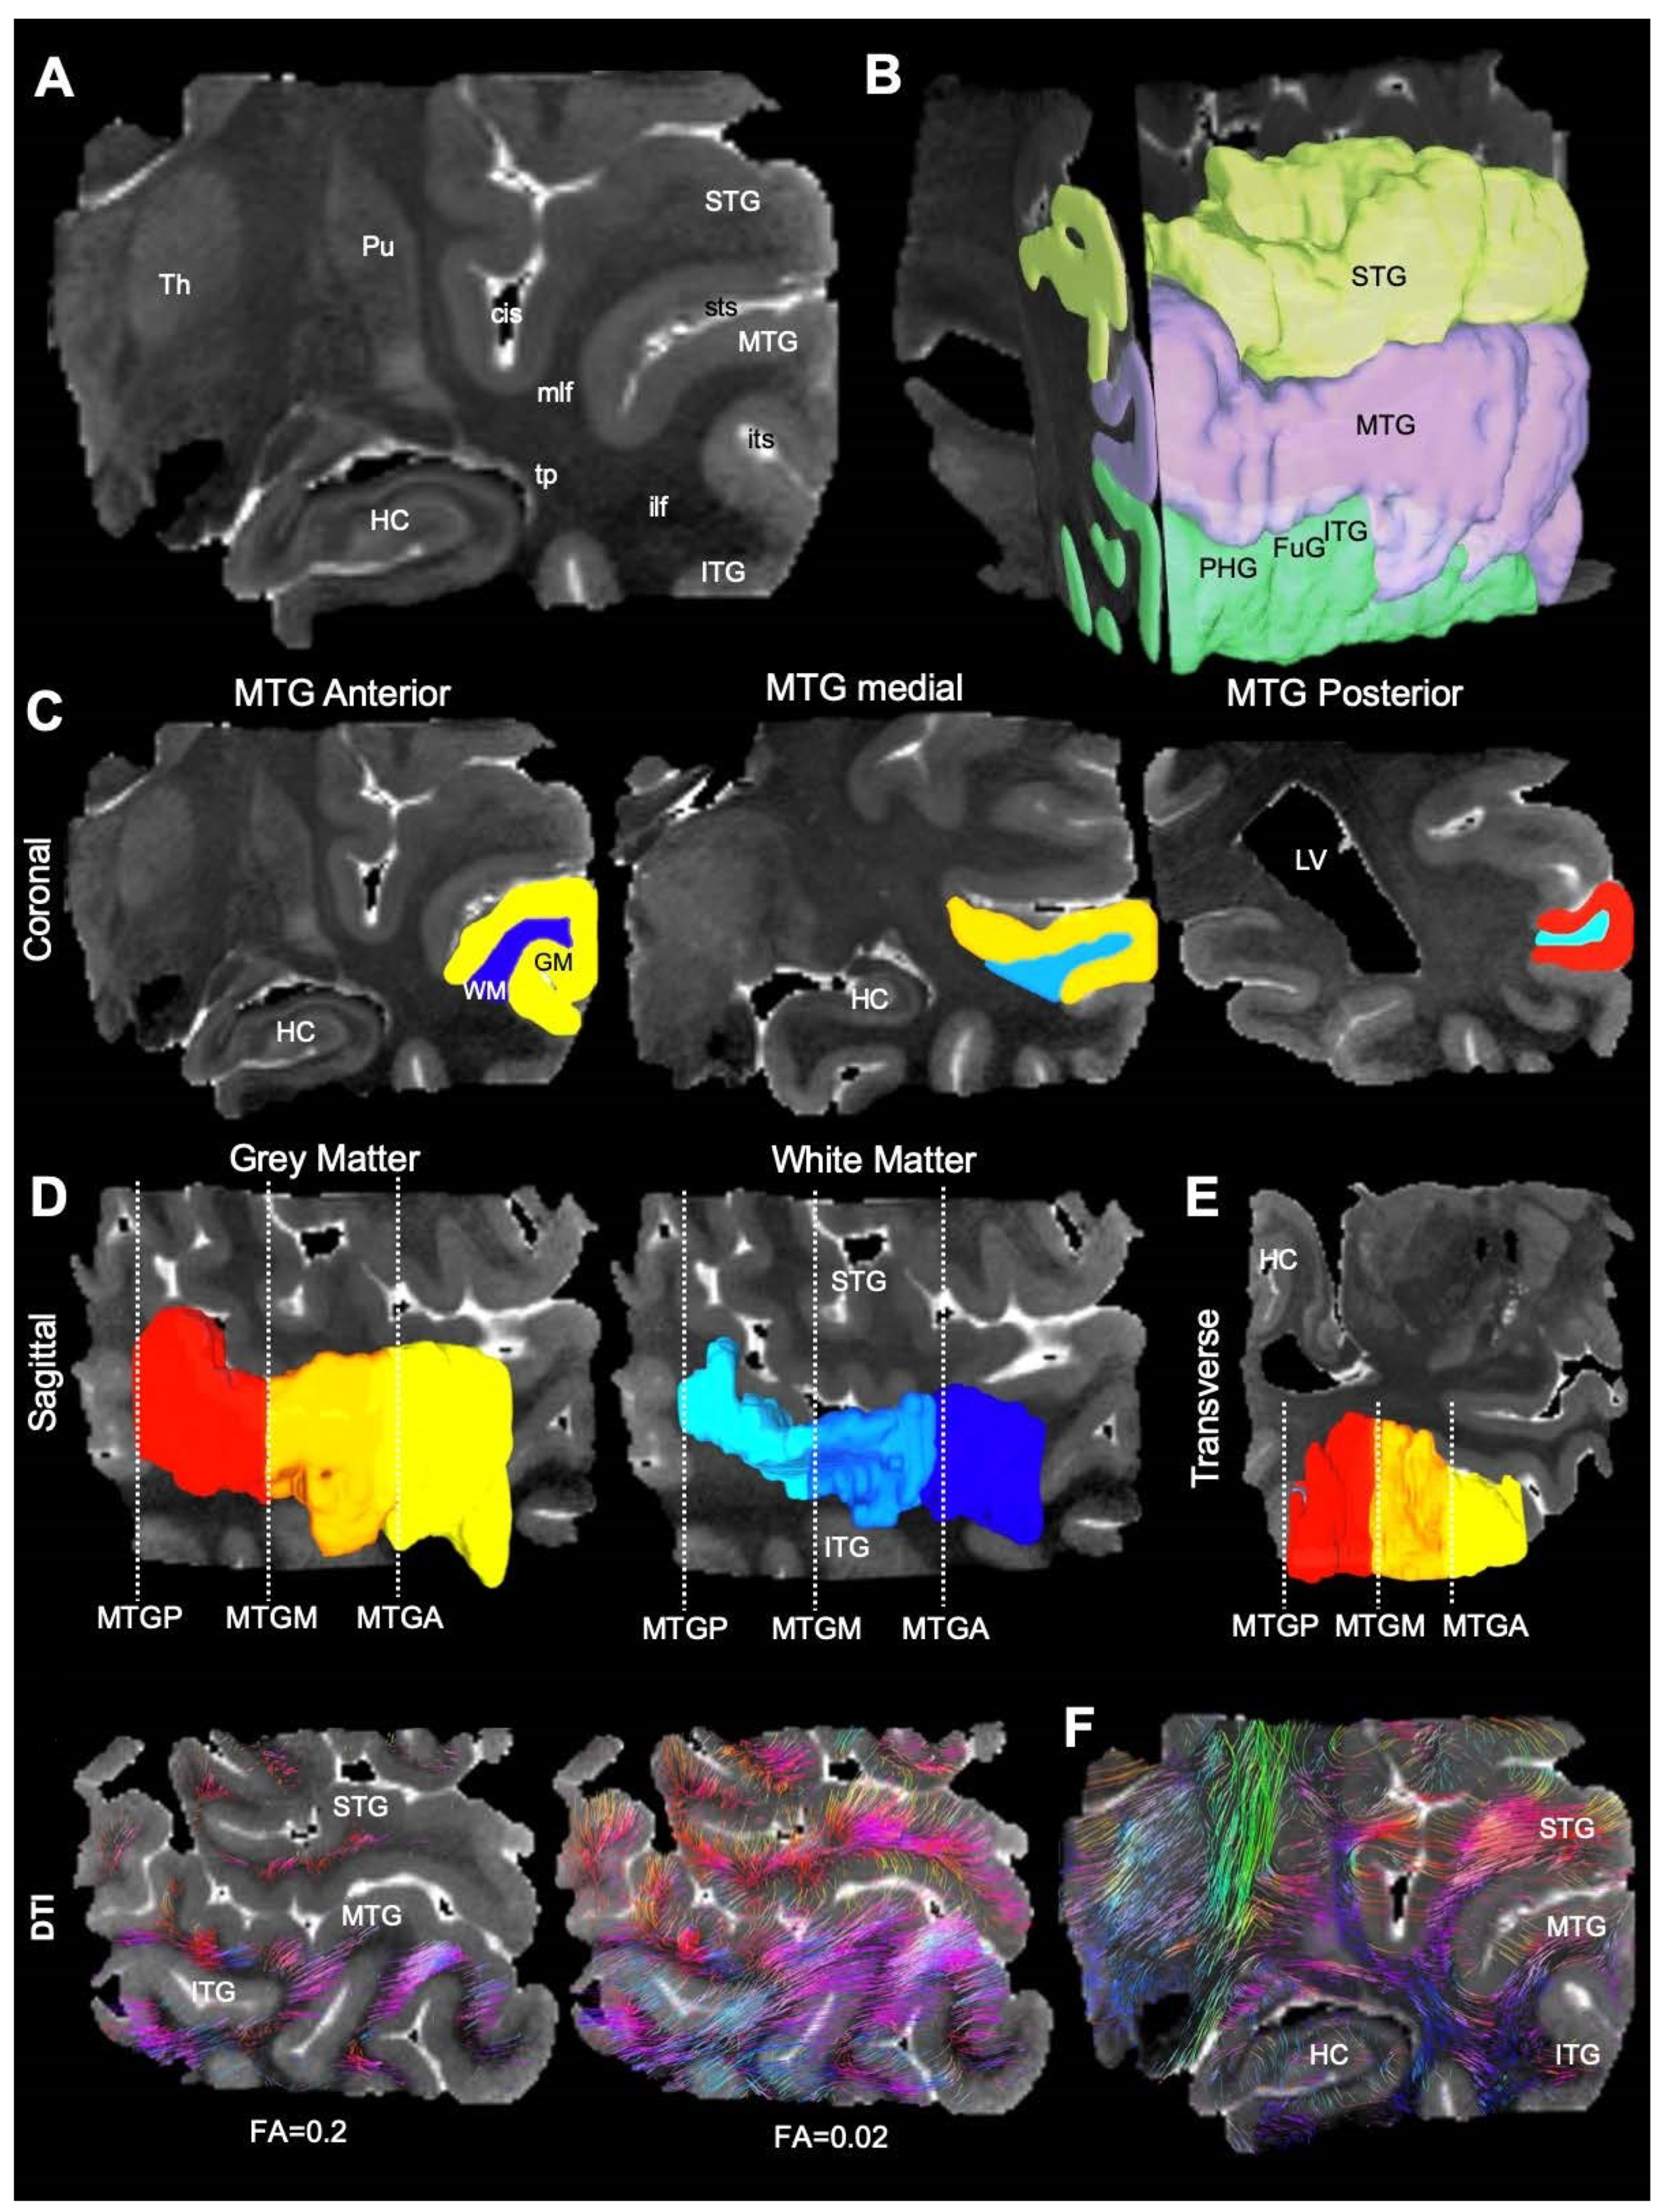

3.1. Magnetic Resonance (MR)-Histology of the Excised Human Cortex

3.2. Mesoscale Diffusion Characteristics of Cortical Dysplasia

3.4. Tractography Reveals Connectivity Changes Associated with Cortical Dysplasia